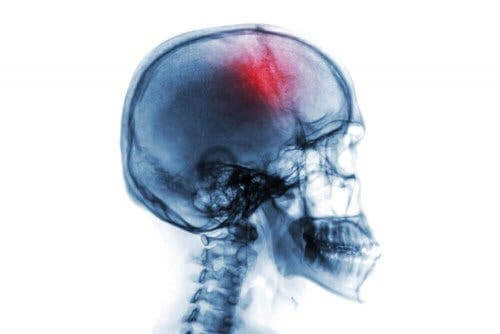

En stroke är ett abrupt neurologiskt syndrom. Det finns många riskfaktorer och symptom på stroke. Det kan antingen vara en blödning eller ett stopp av blodcirkulation i hjärnan.

En blödning eller infarkt kan ske i alla organ och det finns många typer beroende på det drabbade organet. När vi talar om en stroke handlar det om en hjärnblödning eller hjärninfarkt, något som tidigare ofta benämndes slaganfall.

- “Slaganfall” eller “stroke.” Detta innebär att blodflödet till hjärnan upphör. För det första kan det orsakas av en blodpropp i något av blodkärlen som försörjer hjärnan (ischemi). Detta är vanligtvis relaterat till åderförkalkning. För det andra kan det bero på en intracerebral blödning eller hemorragisk stroke (hjärnblödning).